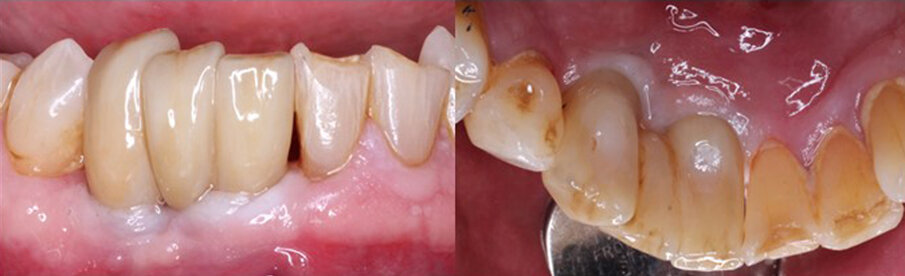

Periapical radiographs were taken to access the conditions present (Figs. 1a & b). A large area of bone loss was noted around the entire root of the canine, which had no osseous support. The lateral incisor presented with 90% bone loss and the central incisor 75% bone loss. The patient was informed that, owing to the amount of bone loss, extraction of the three teeth was the recommended treatment that could be performed on those teeth.

Figs. 1a & b: Pretreatment radiograph demonstrating signicant bone loss associated with the mandibular right central incisor, lateral incisor and canine.